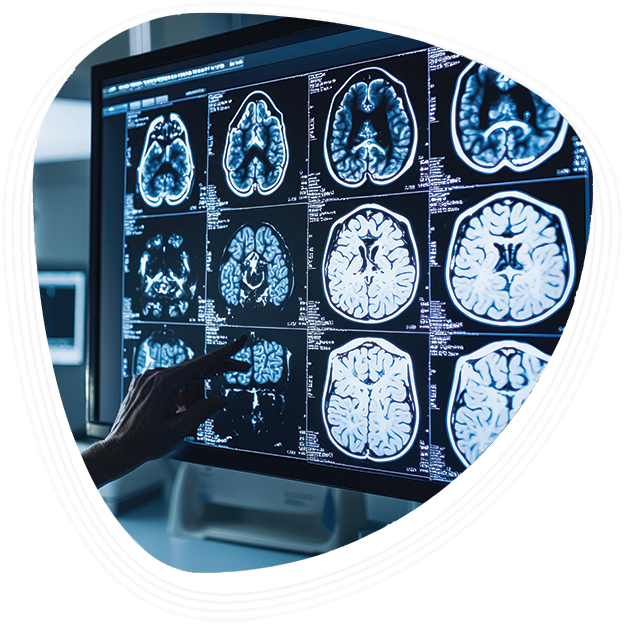

- Advanced imaging such as MRI and CT scans are required for pre-surgical planning.

The brain tumor procedure is planned using detailed imaging such as MRI or CT scans. Neurosurgeons also use tools like intraoperative neuro monitoring and stereotactic navigation to guide surgery safely.